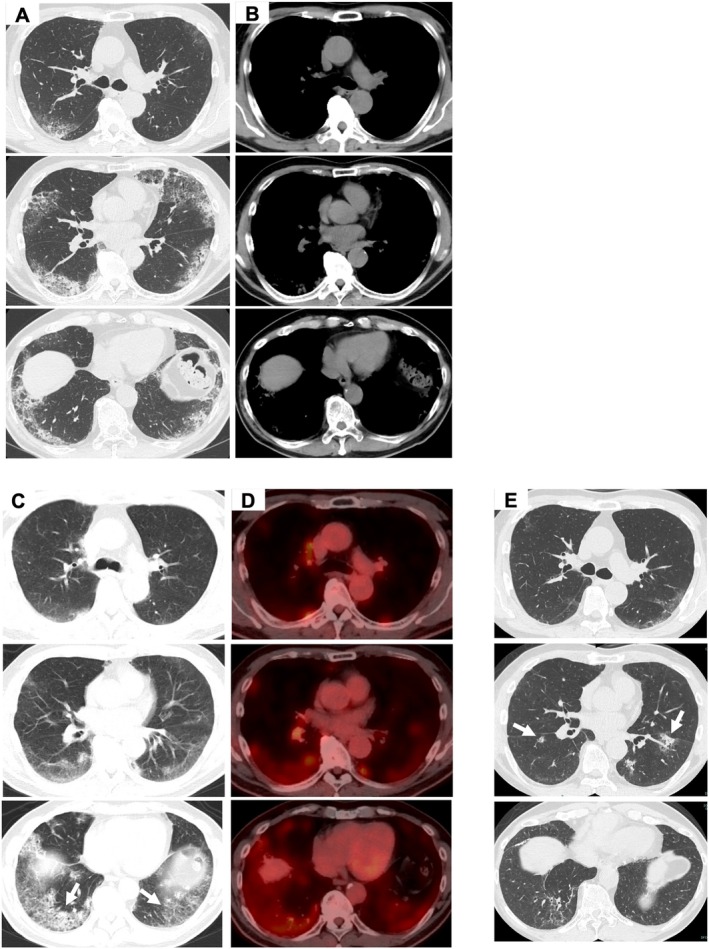

我们报告一个肺泡结节病的病例,在HRCT上显示下叶为主的空域实变和磨玻璃衰减,模拟自发性游荡的特发性间质性肺炎(IIP)。纵隔淋巴结病和葡萄膜炎阴性。手术肺活检显示多发非坏死性肉芽肿。肺泡结节病与IIP相似,但不伴有纵隔淋巴结病变。

We present a case of alveolar sarcoidosis showing lower lobe-predominant areas of airspace consolidation and ground-glass attenuation on HRCT, mimicking idiopathic interstitial pneumonia (IIP) with spontaneous wandering. Mediastinal lymphadenopathy and uveitis were negative. Surgical lung biopsy revealed multiple non-necrotising granulomas. Alveolar sarcoidosis that mimics IIP without mediastinal lymphadenopathy is rare.